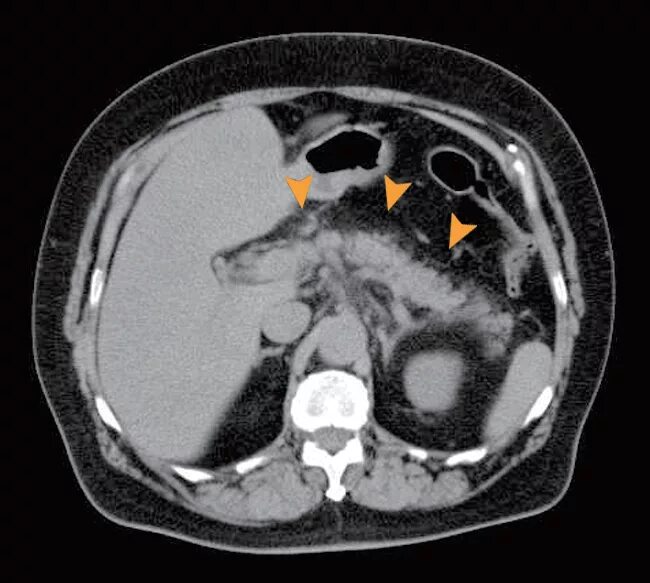

Ct search